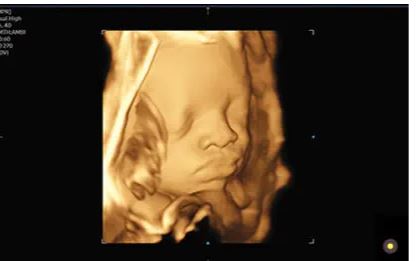

Modes d’imagerie: noir et blanc, doppler couleur, 3D/4D

Technologies d’imagerie redéfinies, optimisées par Crystal Architecture™: Crystal Architecture™ est une architecture d’imagerie qui combine CrystalBeam™ et CrystalLive™ tout en s’appuyant sur S-Vue Transducer™, pour fournir des images d’une clarté cristalline.

– CrystalLive™ est le moteur d’imagerie échographique Samsung le plus récent, avec un traitement d’image 2D, un rendu 3D et un traitement du signal couleur améliorés, dans lequel on obtient des performances d’image enrichies et un flux de travail efficace pendant les cas complexes.